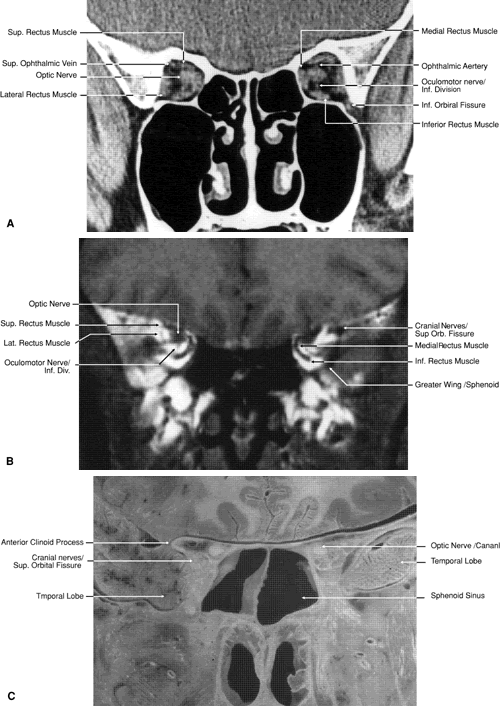

Direct multiplanar CT imaging provides a much improved image over those obtained through multiplanar reconstruction (Fig. 4). This technique is “slice-oriented” in that each image is obtained directly by scanning in a plane perpendicular to the tissue slice whose image is desired. In contrast, multiplanar reconstruction is “volume-oriented” in that the reconstructed images are based on the total volume of tissue imaged in one particular, usually axial, plane. Direct coronal and sagittal CT scanning requires special patient positioning that may not be possible for all patients.1,5,6,15 However, the images produced by direct scanning have significantly higher spatial resolution and quality than those produced by multiplanar reconstruction. In addition, such direct scans avoid imaging artifacts caused by eyelid and ocular movement that often occur in imaging by multiplanar reconstruction. On the other hand, imaging artifacts caused by dental appliances are often present on direct coronal and sagittal scanning. Generally, direct coronal scanning should be obtained, whenever possible, to supplement axial orbital scans to image this area most accurately (Fig. 5). Direct multiplanar imaging of the orbit and optic nerve is particularly helpful in instances of ocular and orbital trauma and in cases in which evaluation of the extraocular muscles, optic nerve, chiasm, canal, and perisellar or cavernous sinus areas is desired.

Fig. 5. Direct coronal computed tomography scan of the midorbit posterior to the globe.

The globe is shown in Figure 12. The orbit and periorbital structures are shown in Figures 13 through 16, and the optic canal is shown in Figures 17 through 26. The cavernous sinus and optic chiasm are shown in Figures 27 and 28, and the posterior visual pathway and cranial nerves are shown in Figures 29 through 33.

Fig. 17. Coronal images through anterior orbit. A. Computed tomography scan. B. T1-weighted magnetic resonance imaging.

Fig. 18. Coronal images through midglobe. A. Computed tomography scan. B. T1-weighted magnetic resonance imaging.

Fig. 19. Coronal images through midorbit posterior to the globe. A. Computed tomography scan.B. T1-weighted magnetic resonance imaging.

Fig. 20. Coronal images through orbital apex. A. Computed tomography scan. B. T1-weighted magnetic resonance imaging. C. Anatomic section of a cadaver head at the level of the orbital apex.